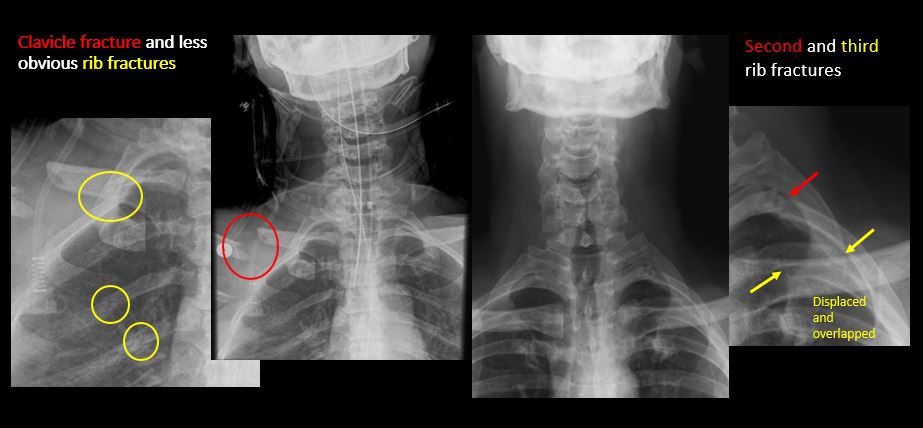

Section 1 Submit Findings C442 Findings Technique The craniocervical junction and/or C7-T1 are not entirely included on the exam. Yes No The exam is over or under penetrated. Yes No The exam is limited by overlying structures, bones or soft tissues, body habitus, patient positioning, support devices, or motion. Yes No Prevertebral and paravertebral soft tissues The soft tissues anterior to C1-C7 are widened or the prevertebral fat stripe is not seen. Yes No The paravertebral soft tissues are abnormally widened. Yes No N/A There is calcification, foreign body, abnormal air, or other abnormal density in the prevertebral or paravertebral soft tissues. Yes No Spinal alignment The distance between the basion and the posterior axial line is > 12 mm. Yes No The distance between the basion and the tip of the dens is > 12 mm. Yes No The atlanto-axial joint distance is > 2 mm on the lateral view. Yes No The distance between the dens and the lateral masses of C1 is abnormally asymmetrically widened on an odontoid or AP view. Yes No N/A The lateral mass(es) of C1 abnormally override(s) the articular pillar(s) of C2 on an odontoid or AP view. Yes No N/A The anterior vertebral body line, posterior vertebral body line, articular pillar line, and/or spinolaminar line is/are abnormal. Yes No The articular pillars or lateral masses, lamina, or other posterior elements are rotated or displaced into the spinal canal or the interlaminar clear zone of the spinal canal. Yes No The visualized spinous processes are malaligned on the AP view or distracted on the lateral view. Yes No There is reversal or straightening of the normal lordosis or abnormal angulation/curvature or motion of the cervical spine on frontal, lateral, flexion and/or extension views. Yes No Vertebral bodies, posterior elements, and base of skull There is a fracture or deformity of the base of the skull or occipital condyles. Yes No There is a fracture or deformity of the anterior or posterior arch of C1. Yes No There is a fracture or deformity of the lateral mass(es) of C1. Yes No There is a fracture or deformity of the dens or C2 vertebral body. Yes No There is a fracture or deformity of the pars interarticularis/articular pillars or other posterior elements of C2. Yes No There is a fracture or distraction of a C3-T1 vertebral body, transverse or spinous process, or other posterior element. Yes No There is evidence of an end plate avulsion or other fracture. Yes No There is displacement of a fracture fragment into the soft tissues, spinal canal, or interlaminar clear zone of the spinal canal. Yes No There is anterior wedging or compression of a vertebral body or end plate. Yes No There is evidence of an aggressive disease process manifest as a lytic, sclerotic, or destructive abnormality of a vertebral body, end plate, pedicle, lamina, articular pillar, transverse or spinous process. Yes No There is focal or diffuse abnormal mineralization. Yes No Disc spaces and facet joints There is distraction or focal widening of a disc space. Yes No There is anterolisthesis, retrolisthesis, subluxation, or rotational abnormality of a disc space. Yes No There is widening, rotational abnormality, or displacement of facets at any motion segment (e.g. locked or jumped, perched facets, or fracture dislocation). Yes No There is disc space narrowing with or without erosive or sclerotic changes of the end plates other than from degenerative change. Yes No There is facet joint narrowing or sclerosis other than from degenerative change. Yes No Additional soft tissues and bones (neck, airway, upper thorax, ribs) The included maxillofacial region, thoracic spine, ribs, or other bones of the upper thorax are abnormal. Yes No There is air or a foreign body or other abnormality in the soft tissues of the lower head, neck or upper thorax. Yes No There is an apical mass, thickening, pleural cap or effusion, or pneumothorax. Yes No N/A The airway is narrowed or displaced. Yes No There are post surgical changes of the bones or soft tissues of the lower head, neck, or upper thorax. Yes No There is an abnormality or complication of post-surgical hardware. Yes No N/A There are support lines or tubes in an abnormal position. Yes No Other findings There are degenerative changes or other existing conditions that might be contributing to symptoms which can or should be further evaluated non-emergently. Yes No